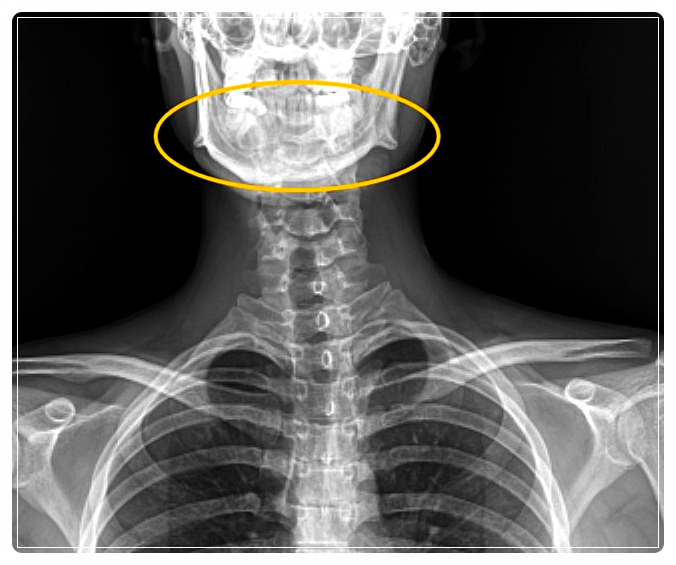

하지만 반복되는 자세와 습관 때문에 턱 주변 근육이 한쪽으로 긴장하면, 장시간 유지되면서 얼굴형 변화가 나타날 수 있습니다.

예를 들어 한쪽으로 수면 자세를 고정하면 밤새 한쪽 관절에 압력이 집중되고, 근육 사용 패턴이 바뀌어 얼굴 비대칭이 뚜렷해지는 경우가 종종 있습니다.

고개가 앞으로 나오는 자세가 반복되면 턱이 자연스럽게 뒤로 밀리면서 관절에 부담이 생깁니다.